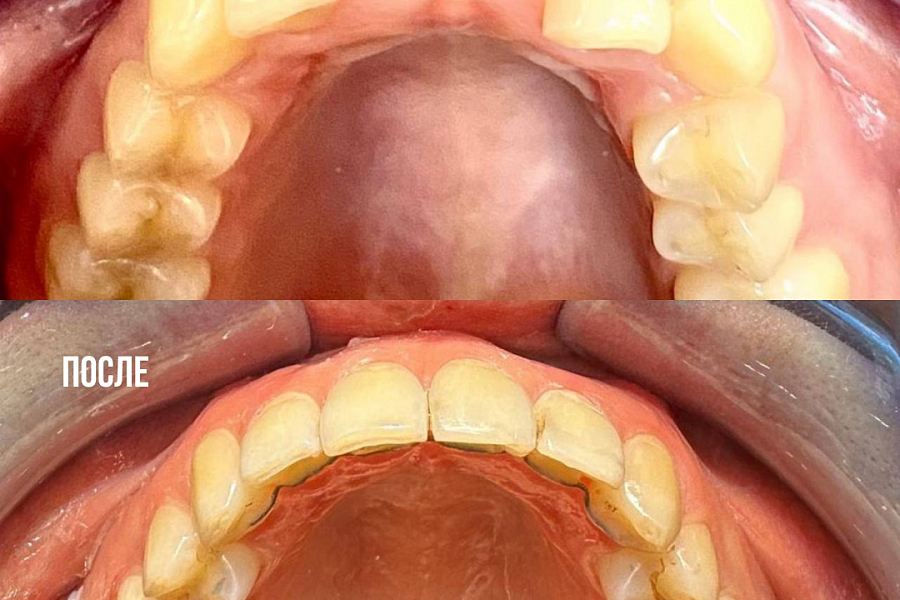

Комплексное гнатологическое и ортодонтическое лечение

Искривление зубных рядов, которое в свою очередь вызывало ряд гнатологических проблем: головная боль, боль в шейном отделе, боль ВНЧС, стираемость эмали и т.д.

Было проведено комплексное гнатологическое и ортодонтичечкое лечение. В результате пациент получил не только красивые ровные зубы, но и избавился от всех сопутствующих проблем.